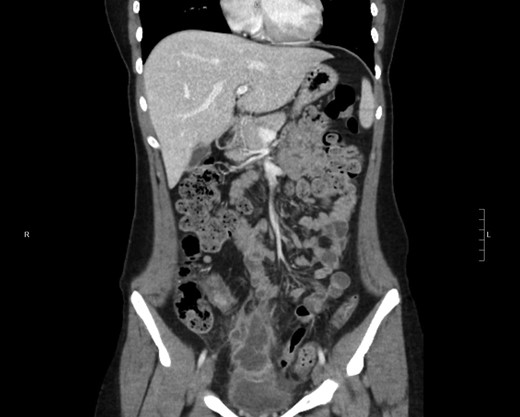

Contrast-enhanced computed tomography CT of the abdomen/pelvis with contrast revealed (Fig. 1) demonstrates 4 × 3.3 × 6.8 cm3 multiloculated enhancing hypodense and isodense mass noted extending superiorly from urinary bladder dome with surrounding acute inflammatory stranding and minimal fluid with possible invasion into the urinary bladder dome (Fig. 2). Secondary thickening of adjacent distal small bowel loop also presented with high probability, and thick walled, dense collapsed urinary bladder seen with per vesical stranding. These findings with the clinical presentation was further evaluated and differential diagnosis of patent urachus, urachal sinus, urachal diverticulum and malignant transformation of the cyst was aided and diagnostic laparoscopy surgery was planned.

Coronal plan of CT abdomen/pelvis showing the urachal cyst above bladder.